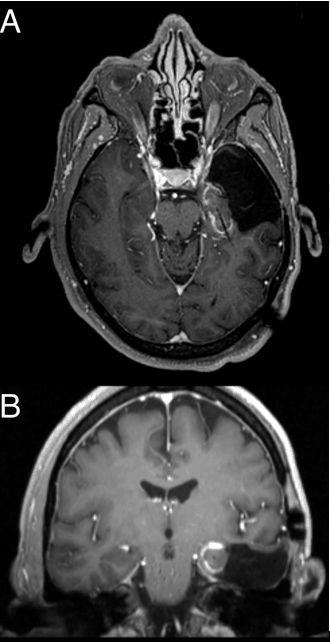

Figure 3: Post-ablation images; Enhancement surrounding the ablation area in the (A) axial and (B) coronal sections.